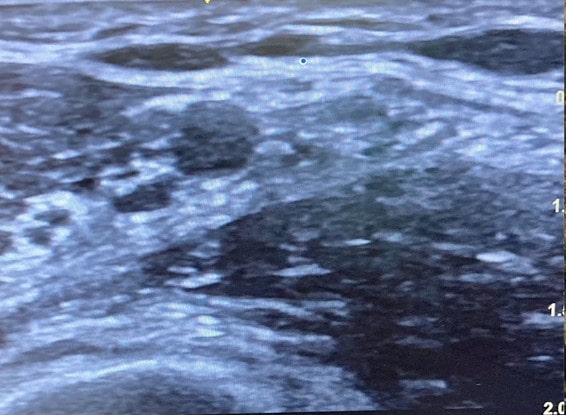

La imagen ecográfica típica del espacio axilar es la que se observa aquí:

- Localizamos la arteria axilar como una estructura pulsátil, anecoica y de forma circular. En la parte baja de la imagen observaremos una estructura redondeada hiperecogénica que se corresponde al húmero. Lateralmente a la arteria veremos dos estructuras musculares que se corresponden al músculo bíceps y el músculo córaco-braquial. Otras estructuras típicas son el músculo redondo mayor que se localiza profundamente y medial respecto a la arteria y vena axilar.

- Los nervios se van a visualizar de diferentes maneras, siendo la más común la aparición de estructuras hiperecoicas redondeadas u ovales rodeadas de un refuerzo hiperecogénico que corresponde al epineuro, en una disposición como de panal de abejas.